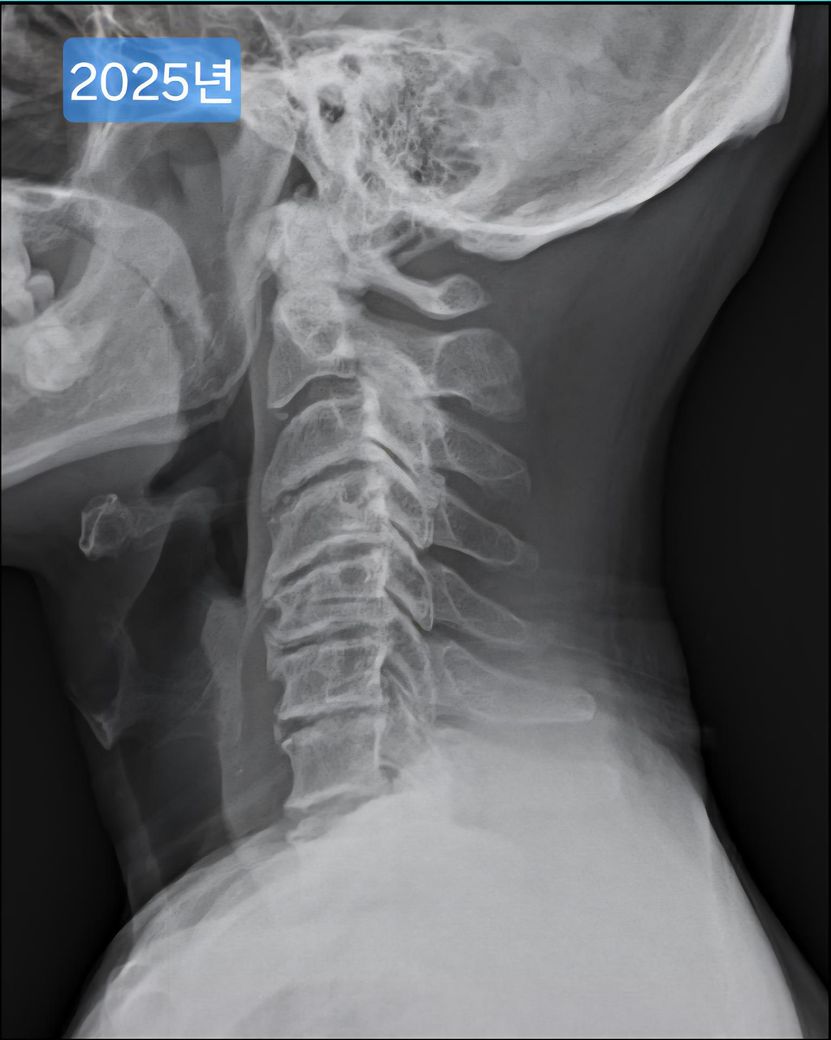

선생님이 같이 찍힌 목사진을 보시더니 심각하다며..경추사이 간격도 좁고, 일자목이고..

며칠전 찍은 2025년도 엑스레이와 9년전 사진을 업로드 해 드리겠습니다.

(이미지에 좌측상단에 해당연도 표시했습니다.)

• 4번 째 사진